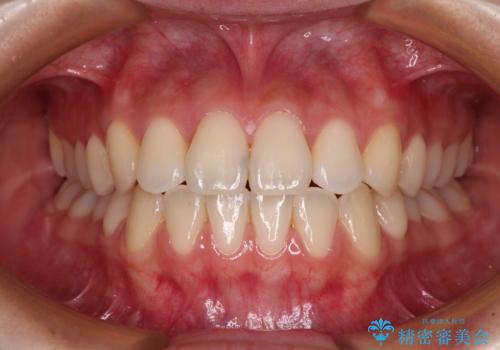

前歯の反対咬合をワイヤー矯正で改善して噛みやすく